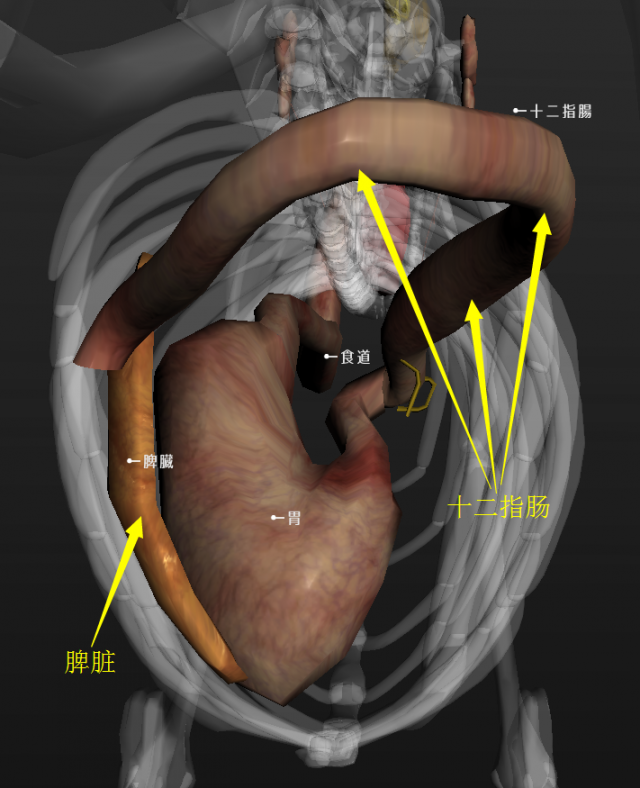

犬的食道、胃、十二指肠的形态与位置(后侧观) |

资源描述:犬的食道、胃、十二指肠的形态与位置(后侧观)

文件来源:吴礼平

从后向前方看,在食管末端的胃沿顺时针方向可旋转90°~360°,这种旋转使幽门偏向中线的左侧,使十二指肠进入食管末端和胃之间。根据不同的扭转程度,脾脏可能在不同的位置从腹腔左前部到达后部。当胃扭转大于180°时,会使贲门闭塞。